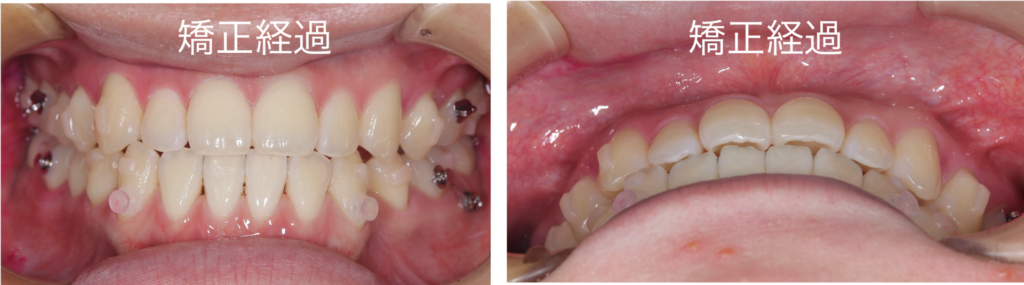

マウスピース矯正による治療経過になります

反対咬合は改善され、正常な咬み合わせに改善することができました

今回、患者様は非常にしっかりとマウスピースを着用していただけたため、12か月という短期間でここまで改善することができました